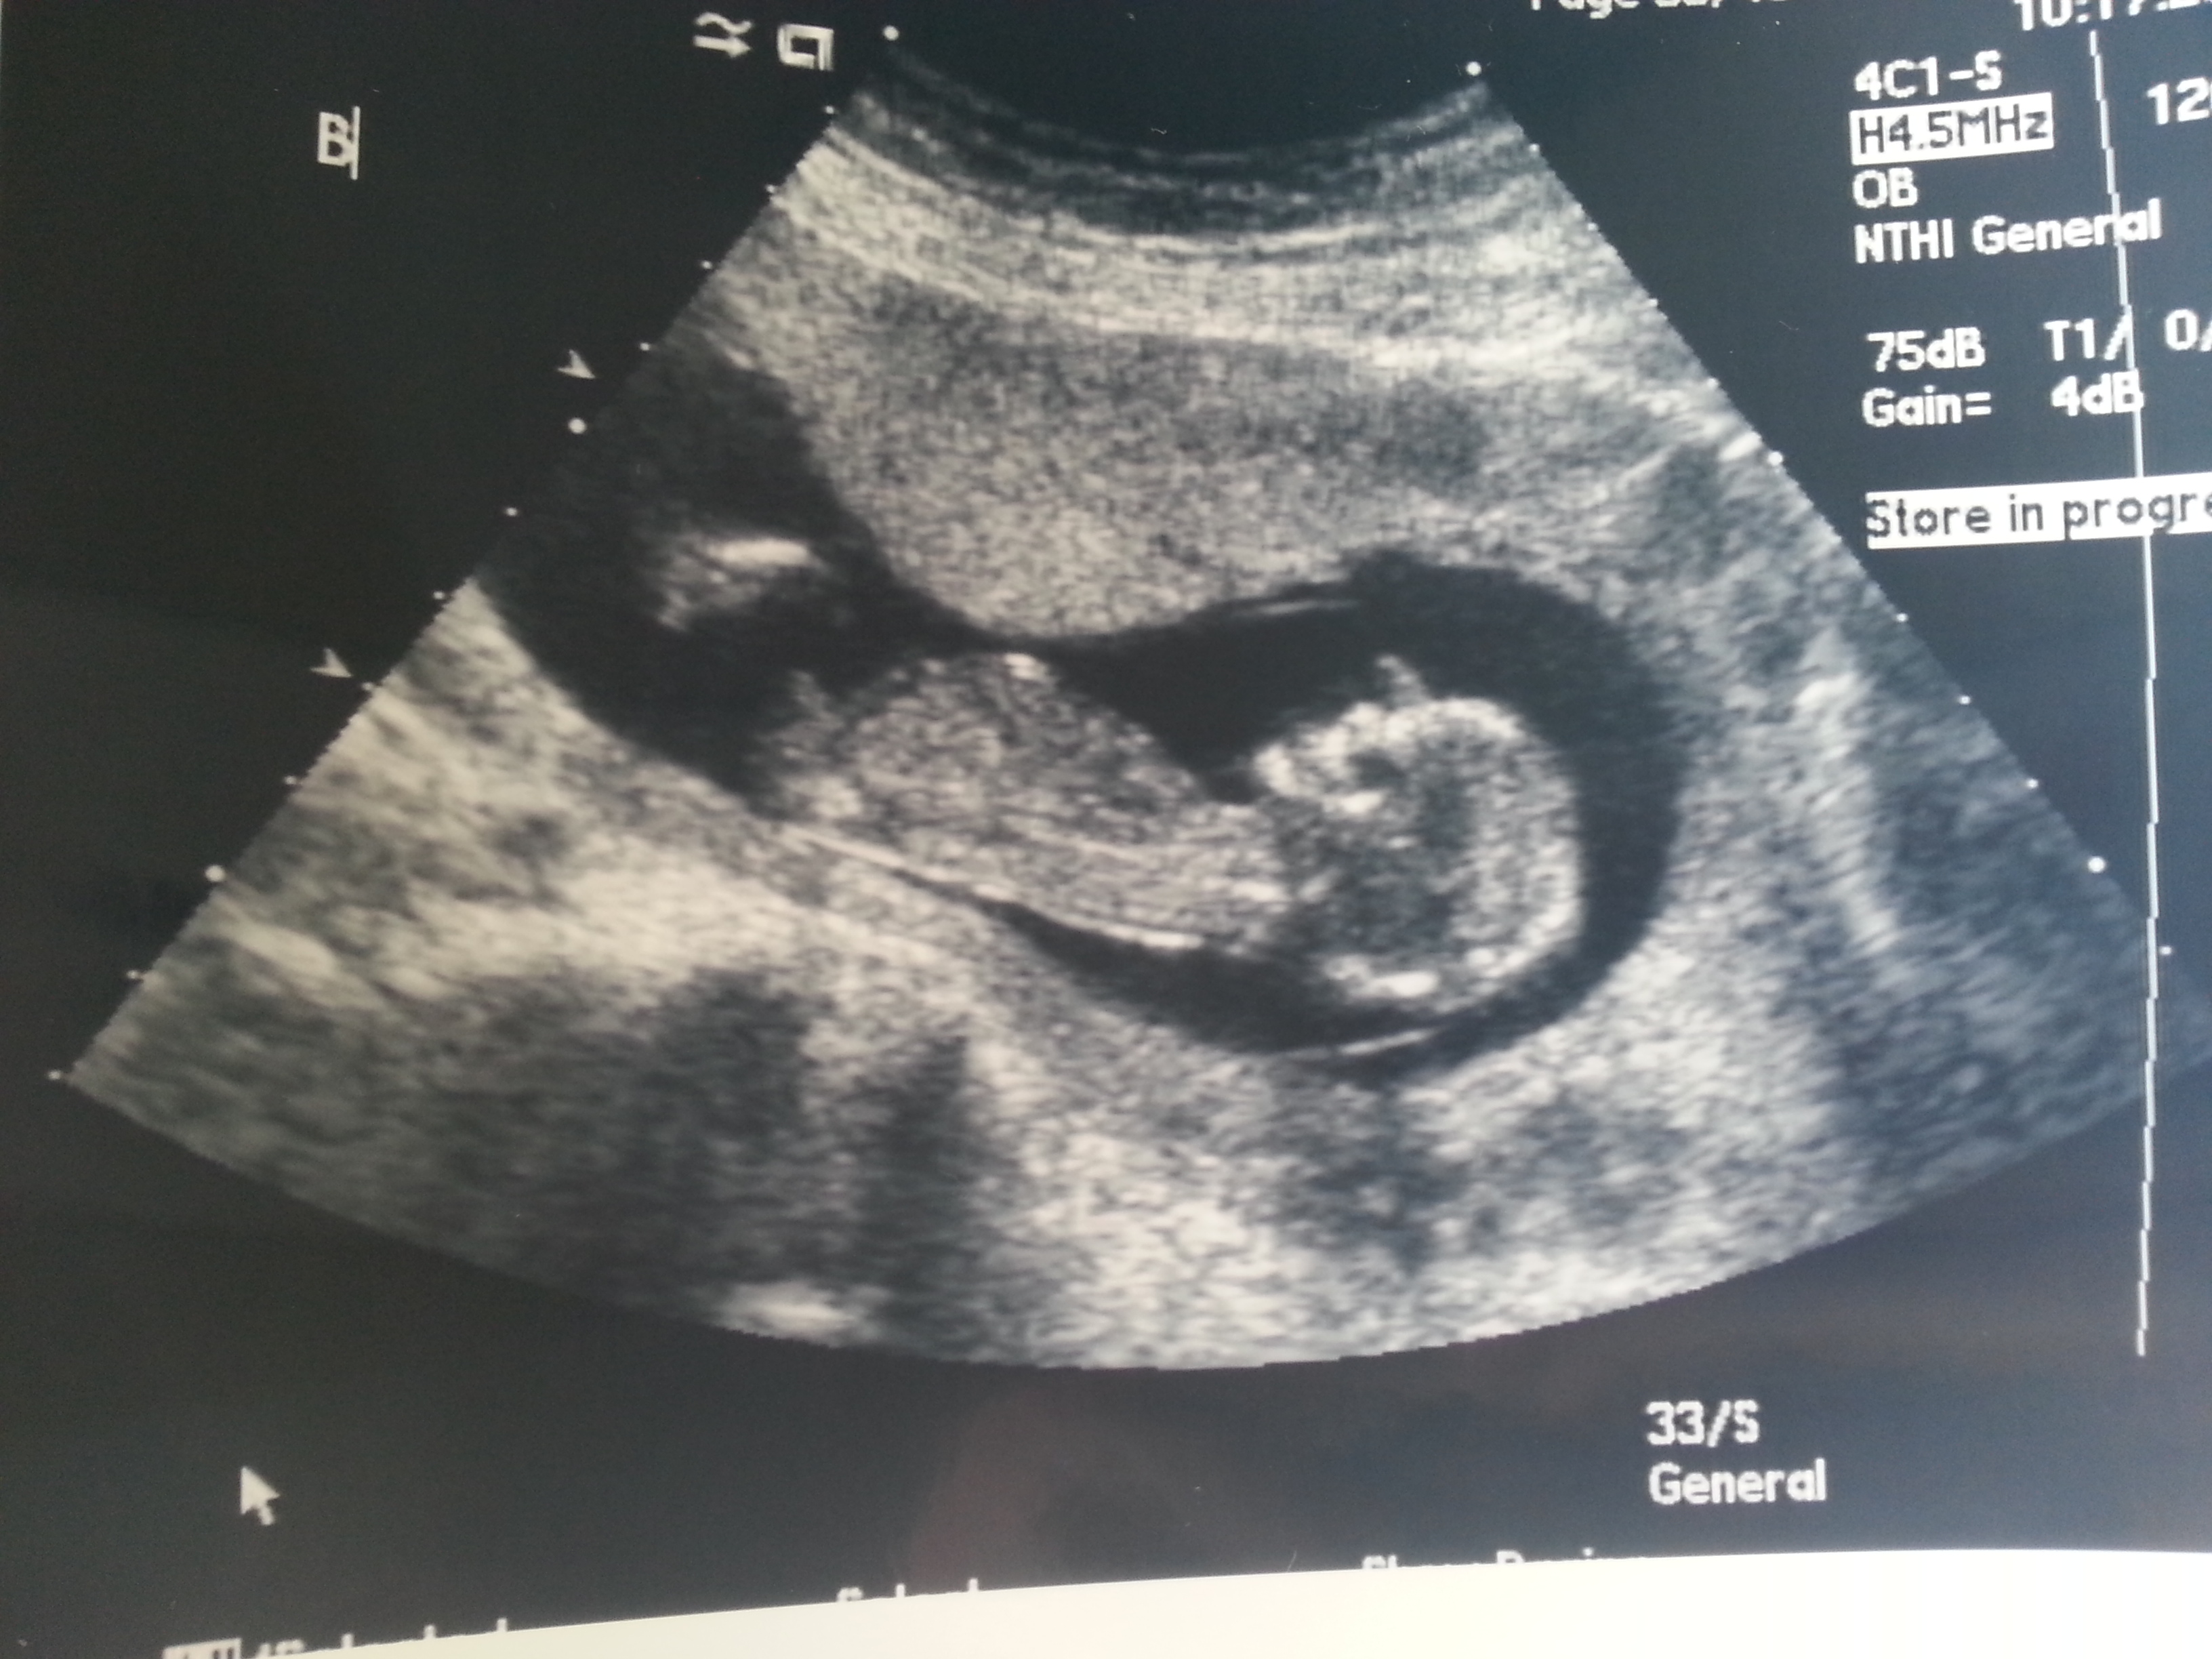

I was 12weeks 6 days and measuring 13weeks 3 days.

Maybe boy/girl. Not the best shots though!

I think B is a boy and A is a girl.

I think B is a boy, A could go either way but I lean boy.